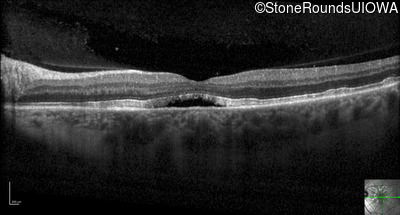

Optical Coherence Tomography - Left - 20/25 +2

Exemplar / OCT Stack